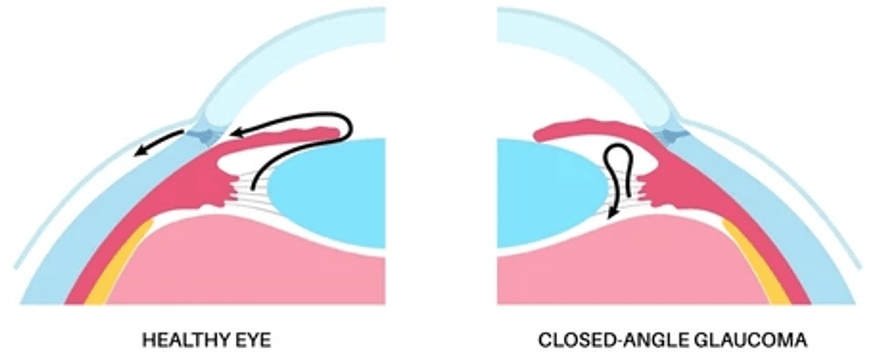

– Glaucome à angle fermé : ce type est moins courant, mais constitue une urgence médicale. Il touche particulièrement les patients forts hypermétropes ou avec une cataracte avancée. Dans l’angle fermé, l’angle entre l’iris et la cornée est trop étroit, bloquant le drainage du liquide intraoculaire (humeur aqueuse) et provoquant une montée rapide de la PIO. Les symptômes incluent des douleurs oculaires sévères, des nausées, une vision floue, et des halos autour des lumières. Sans intervention immédiate, ce type de glaucome peut entraîner une perte rapide de la vision.